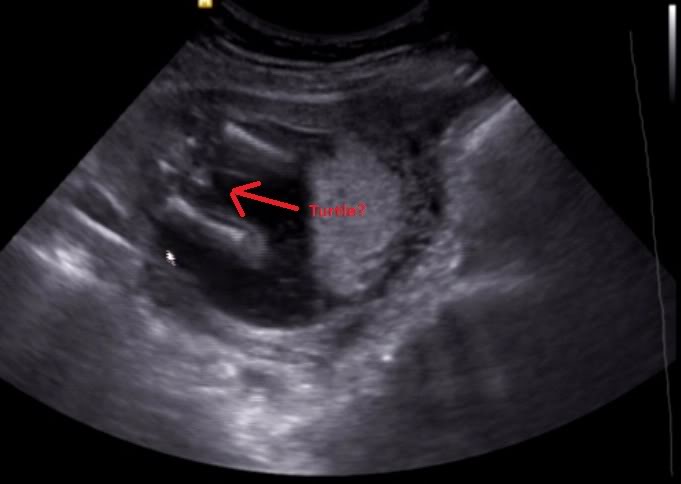

Today at 16 weeks I was told it is looking more like a little boy.

Can you please have a look and tell me what you think.

16 week scan

Attachment 12857